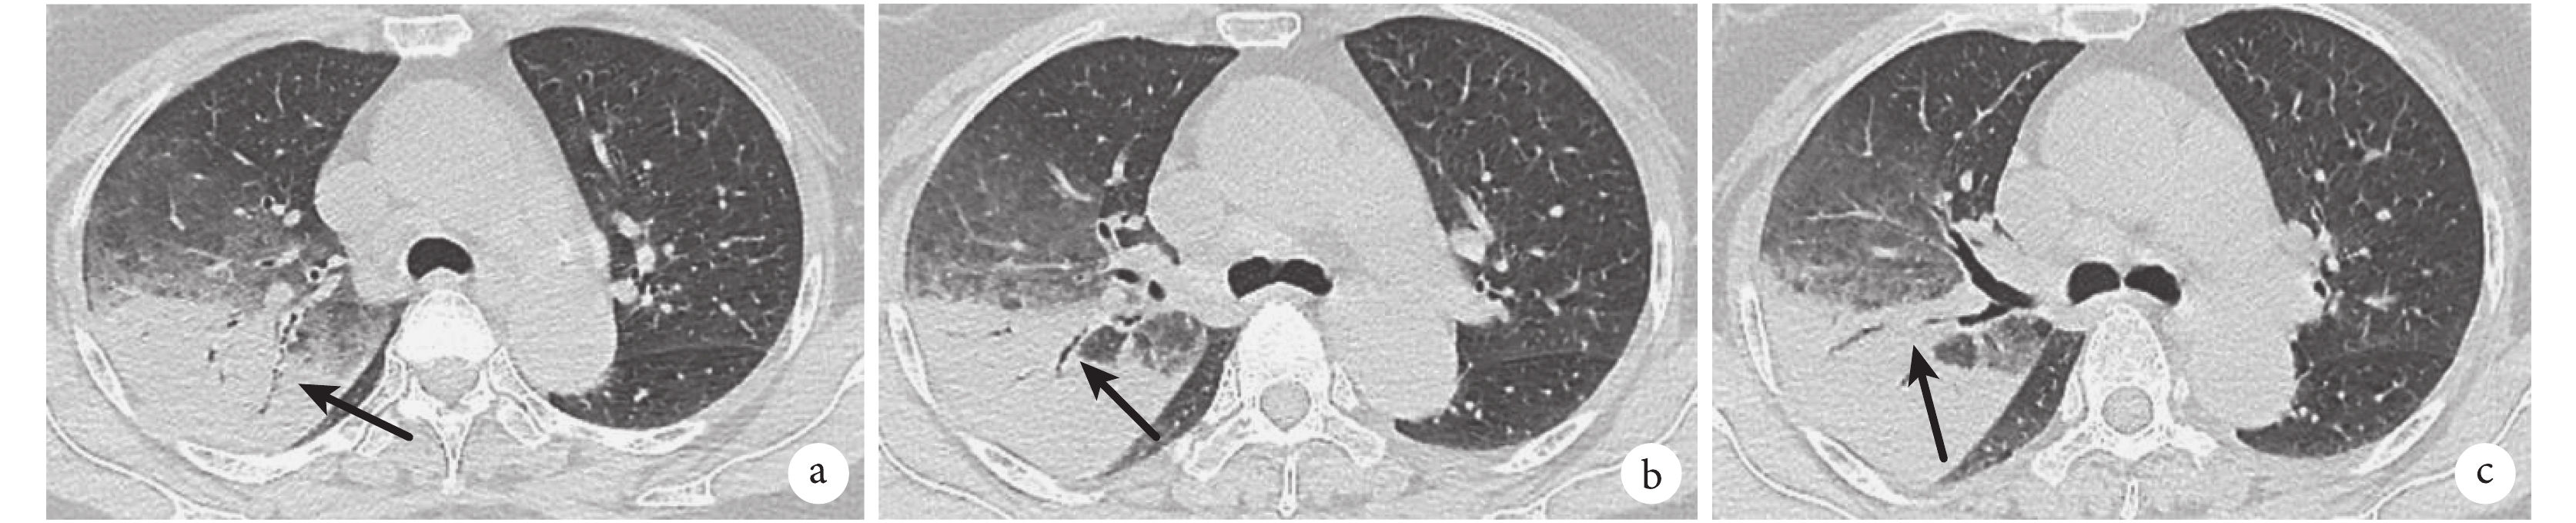

患者,女,41 歲,支氣管鏡肺活檢病理示機化性肺炎改變,結合臨床及影像學表現診斷為 COP。a. 兩肺沿支氣管血管周圍分布的實變影,左肺可見走形完整的 EABG,伴有牽拉性支氣管擴張改變(黑箭),部分實變影呈反暈征樣改變(白三角);b. 兩肺可見少量走形中斷的斷續 ABG(白箭)。c、d. 糖皮質激素治療后 8 d 后,復查胸部 HRCT 示兩肺實變病灶較前稍吸收

圖 1~4 展示了 2 例 CAP 及 2 例 OP 患者的胸部 HRCT 影像學特征。在實變影的分布上,69.6% 的 OP 患者呈雙側分布,顯著高于 CAP 組的 30.3%(χ2=22.412,P=0.000)。分別有 41.4% 和 16.1% 的 OP 患者實變影呈胸膜下(圖 1)、支氣管血管周圍(圖 2)分布,在 CAP 組分別為 19.2% 和 1.0%,差異有統計學意義(χ2=8.886,P=0.003;P=0.000)。87.5% 的 OP 患者胸部 HRCT 上有數量不等、形態各異的 ABG,顯著高于 CAP 組的 72.7%(χ2=4.558,P=0.033)。OP 患者的 ABG 數量的中位數及四分位數間距為 4(2~8),顯著高于 CAP 組的數量 2(0~4)(z=3.640,P=0.000)。在形態上,58.9% 的 OP 患者存在 EABG(圖 1b、圖 2a),顯著高于 CAP 組的 21.2%(χ2=22.413,P=0.000)。26.3% 的 CAP 患者有斷續 ABG(圖 3、圖 4),16.1% 的 OP 患者有斷續 ABG(圖 2b),差異無統計學意義(χ2=2.125,P=0.148)。

間質性肺炎的其他征象如牽拉性支氣管擴張(圖 1b、圖 2a)、磨玻璃影(ground glass opacity,GGO)在 OP 患者中更多見,分別為 26.8% 和 39.3%,而在 CAP 組僅為 1.0% 和 11.1%。1.0% 的 CAP 患者有反暈征,顯著低于 OP 組的 26.8%(圖 1a、圖 2a)(χ2=25.671,P=0.000)。胸腔積液(圖 3)和支氣管壁增厚(圖 4b)在 CAP 患者中更常見,為 56.6% 和 35.4%。其他影像學特征詳見表 3。